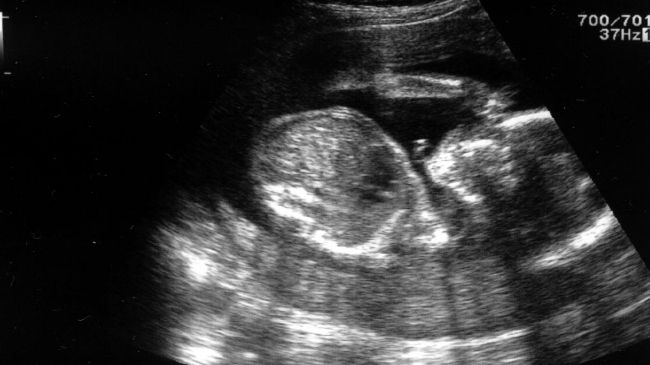

22 nov. 2016, 11:08Ultimele StiriÎnsărcinată, a făcut ecografie la 12 săptămâni. Medicii s-au îngrozit: Ăsta nu e un copil